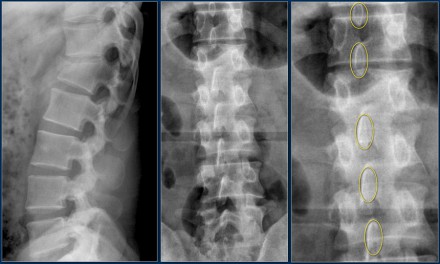

Widening of the interpedicular distance

Widening of the interpedicular distance, often a result of the sagittal fracture, is seen in 80% of burst fractures.

The lateral view shows the typical features of a burst fracture.

On the AP-view notice the subtle widening of the interpedicular distance compared to the levels above and below.

The axial CT and MRI in the same patient show the displaced fragment pressing on the thecal sac.

On the sagittal CT and MRI there are no signs of posterior ligamentous injury.